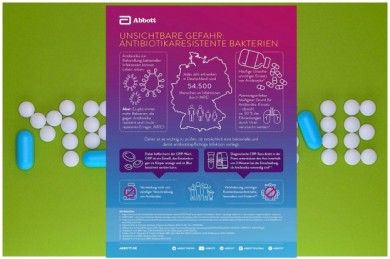

Medizin & Pharma

©Pixabay, Grafik: Abbott

©Pixabay, Grafik: Abbott

Passend zu unserem Beitrag über die Phagenforschung ist die Meldung der Firma Abbott zu diesem Thema. Denn die weltweit zunehmende Verbreitung von Bakterien, die gleich gegen mehrere Antibiotika resistent sind, ist eine der größten Herausforderungen …

Abbott